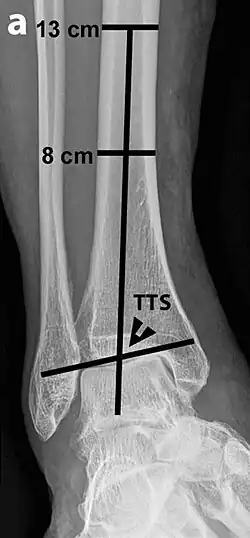

The initial evaluation of suspected ankle pathology is usually by projectional radiography ("X-ray").

Varus or valgus deformity, if suspected, can be measured with the frontal tibiotalar surface angle (TTS), formed by the mid-longitudinal tibial axis (such as through a line bisecting the tibia at 8 and 13 cm above the tibial plafond) and the talar surface.[25] An angle of less than 84 degrees is regarded as talipes varus, and an angle of more than 94 degrees is regarded as talipes valgus.[26]